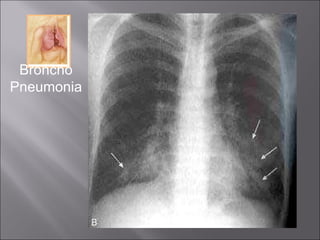

Extremes of age. (infancy and old age) Staph, Strep, Pneumo & H. influenza Patchy consolidation –  not limited to lobes . Suppurative inflammation Usually bilateral Lower lobes common

Broncho Pneumonia

Extremes of age.(infancy and old age) Staph, Strep, Pneumo & H. influenza Patchy consolidation – not limited to lobes . Suppurative inflammation Usually bilateral Lower lobes common